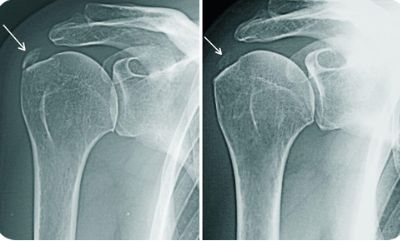

Травма плеча

Любая травма плеча влечет за собой возникновение болевого синдрома в месте повреждения с иррадиацией боли в ближайшие области.

Характер и локализация боли

Характер боли зависит от вида полученной травмы. Так, например, при ушибе боль описывается как умеренная, тупая. При вывихе и переломе боль сильная, острая, усиливается при попытках двигать рукой и плечом.

Дополнительные симптомы

Симптоматика также зависит от вида травмы. Чаще всего травму сопровождают:

- отечность и покраснение кожи над областью повреждения;

- образование гематомы;

- визуальная асимметрия плечевых суставов (при переломах и вывихах) и пр.

Диагностика и лечение

Диагностика сводится к осмотру, пальпации и рентгенографии.

Лечение назначается травматологом в зависимости от того, какая травма предшествовала возникновению боли.